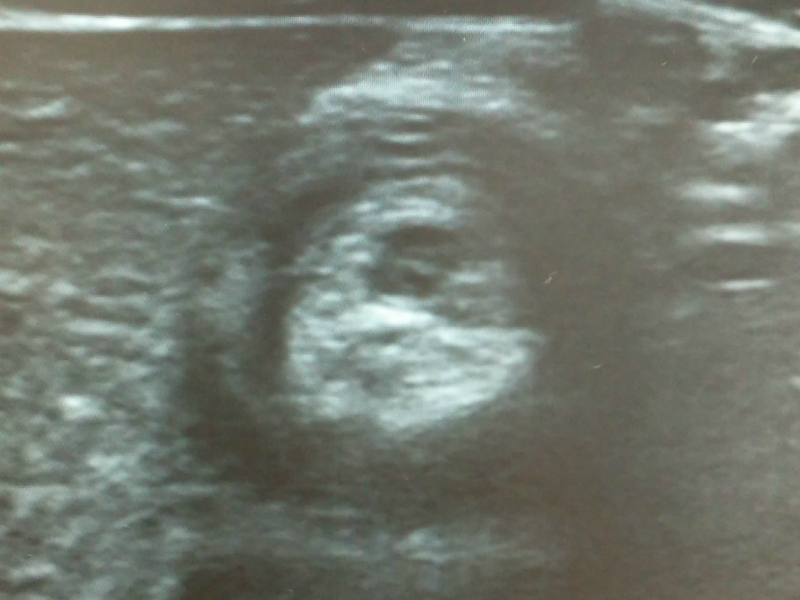

진단은 타겟 사인(target sign)이라고 해서 초음파로 장이 겹쳐져 막힌 부분을 확인하는 것이고 치료는 항문을 통해 공기나 조영 물질을 섞은 액체로 장을 밀어내어 펴주는 치료를 하게 됩니다. 간혹 관장 정복에 실패하거나 장천공이 발생하면 수술적 치료가 필요한 경우도 생깁니다.

021104.png